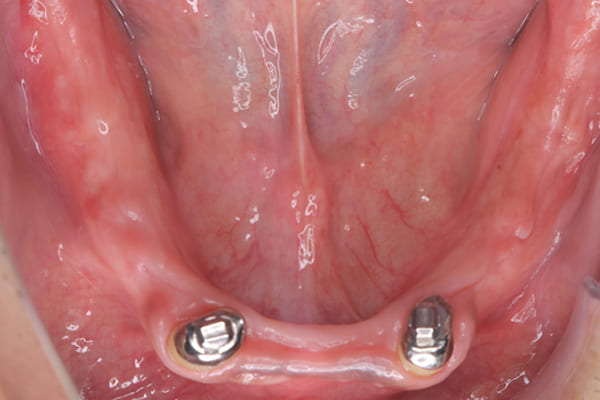

治療後に入れ歯を外した下顎

-

治療後に入れ歯を装着した下顎

下の総入れ歯は外れやすいため大きな虫歯はありましたが、虫歯治療を行い、根のみ残せた2本の歯に磁石を利用することで歌われた際も外れない入れ歯の設計としました。

下顎は舌があるため、上顎と比較すると総入れ歯の場合、外れやすい傾向があります。患者様はまだお若く、お肉がお好きだったとのこと、またお歌もご趣味とのことで、ご相談の上、なるべく外れない設計としました。

磁石を用いた入れ歯の設計により上下の入れ歯は、お食事やお歌を歌われ大きなお口を開けても外れない状態が可能になりました。